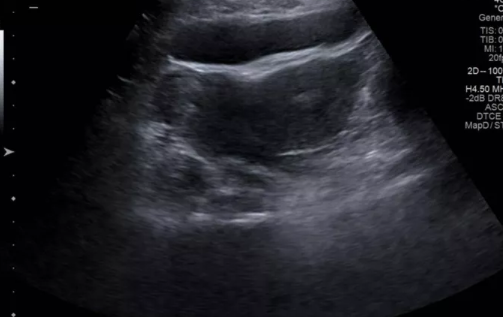

超聲表現:

橫切面子宮橫徑增寬,宮底部中央凹陷,凹陷深度大于宮壁厚度的50%,左右見兩突出的宮角。

宮底部子宮內膜分離,子宮下段至宮頸子宮內膜形態正常。

診斷注意:須注意和子宮肌瘤及卵巢腫物鑒別,特別是一側妊娠時,要注意是否有宮腔線。

雙角子宮與縱隔子宮鑒別:兩者主要是從子宮外形上予以區別,前者宮底較寬,兩宮角有一較深外形似羊角的凹陷,兩側各具一宮腔,典型橫切面為心形凹陷,宮體下段宮頸水平橫切面聲像圖無異常;后者外形正常,但宮底橫徑較寬,其兩側各有一內膜回聲。